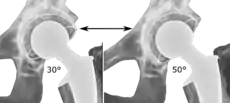

The direction of the acetabular cup influences the range of motion of the leg, and also affects the risk of dislocation.[9] For this purpose, the acetabular inclination and the acetabular anteversion are measurements of cup angulation in the coronal plane and the sagittal plane, respectively.

Acetabular anteversion.[81] This parameter is calculated on a lateral radiograph as the angle between the transverse plane and a line going through the (anterior and posterior) margins of the acetabular cup.[81]

Acetabular anteversion is normally between 5 and 25°.[9] An anteversion below or above this range increases the risk of dislocation.[9] There is an intra-individual variability in this method because the pelvis may be tilted in various degrees in relation to the transverse plane.[9]